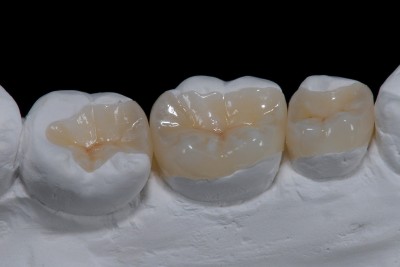

Les Inlays/Onlays

Notre objectif commun est la conservation de l'organe dentaire dans son intégralité. Notre philosophie de pratique est la réalisation de soins les moins mutilants possibles, esthétiques et qui résistent dans le temps. Le développement des...

Carie dentaire nettoyée, étanchéifiée avec une digue dentaire et mise en place de la matrice

Soin dentaire des petites et moyennes caries avec de la résine composite stratifiée en technique de restauration directe

Le cabinet dentaire Maupassant à Marseille propose des traitements efficaces pour les petites et moyennes caries avec la résine composite stratifiée. Découvrez nos solutions durables et adaptées pour restaurer vos dents, ainsi que des soins spécialisés pour les caries plus importantes.